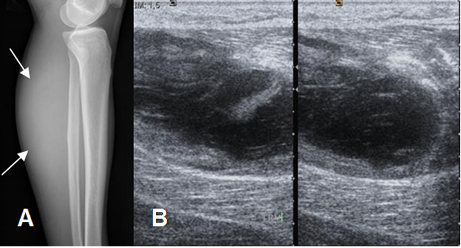

Fig 208. Hematoma muscular.

A: Rx lateral de pierna. Prominencia en los tejidos blandos de la región posterior.

B: Ecografía axial. Colección líquida dentro del músculo gemelo, por hematoma.